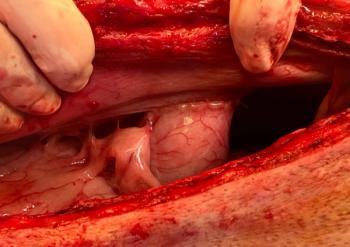

The 5-year-old canine's left hind leg was treated after experiencing vehicular trauma.